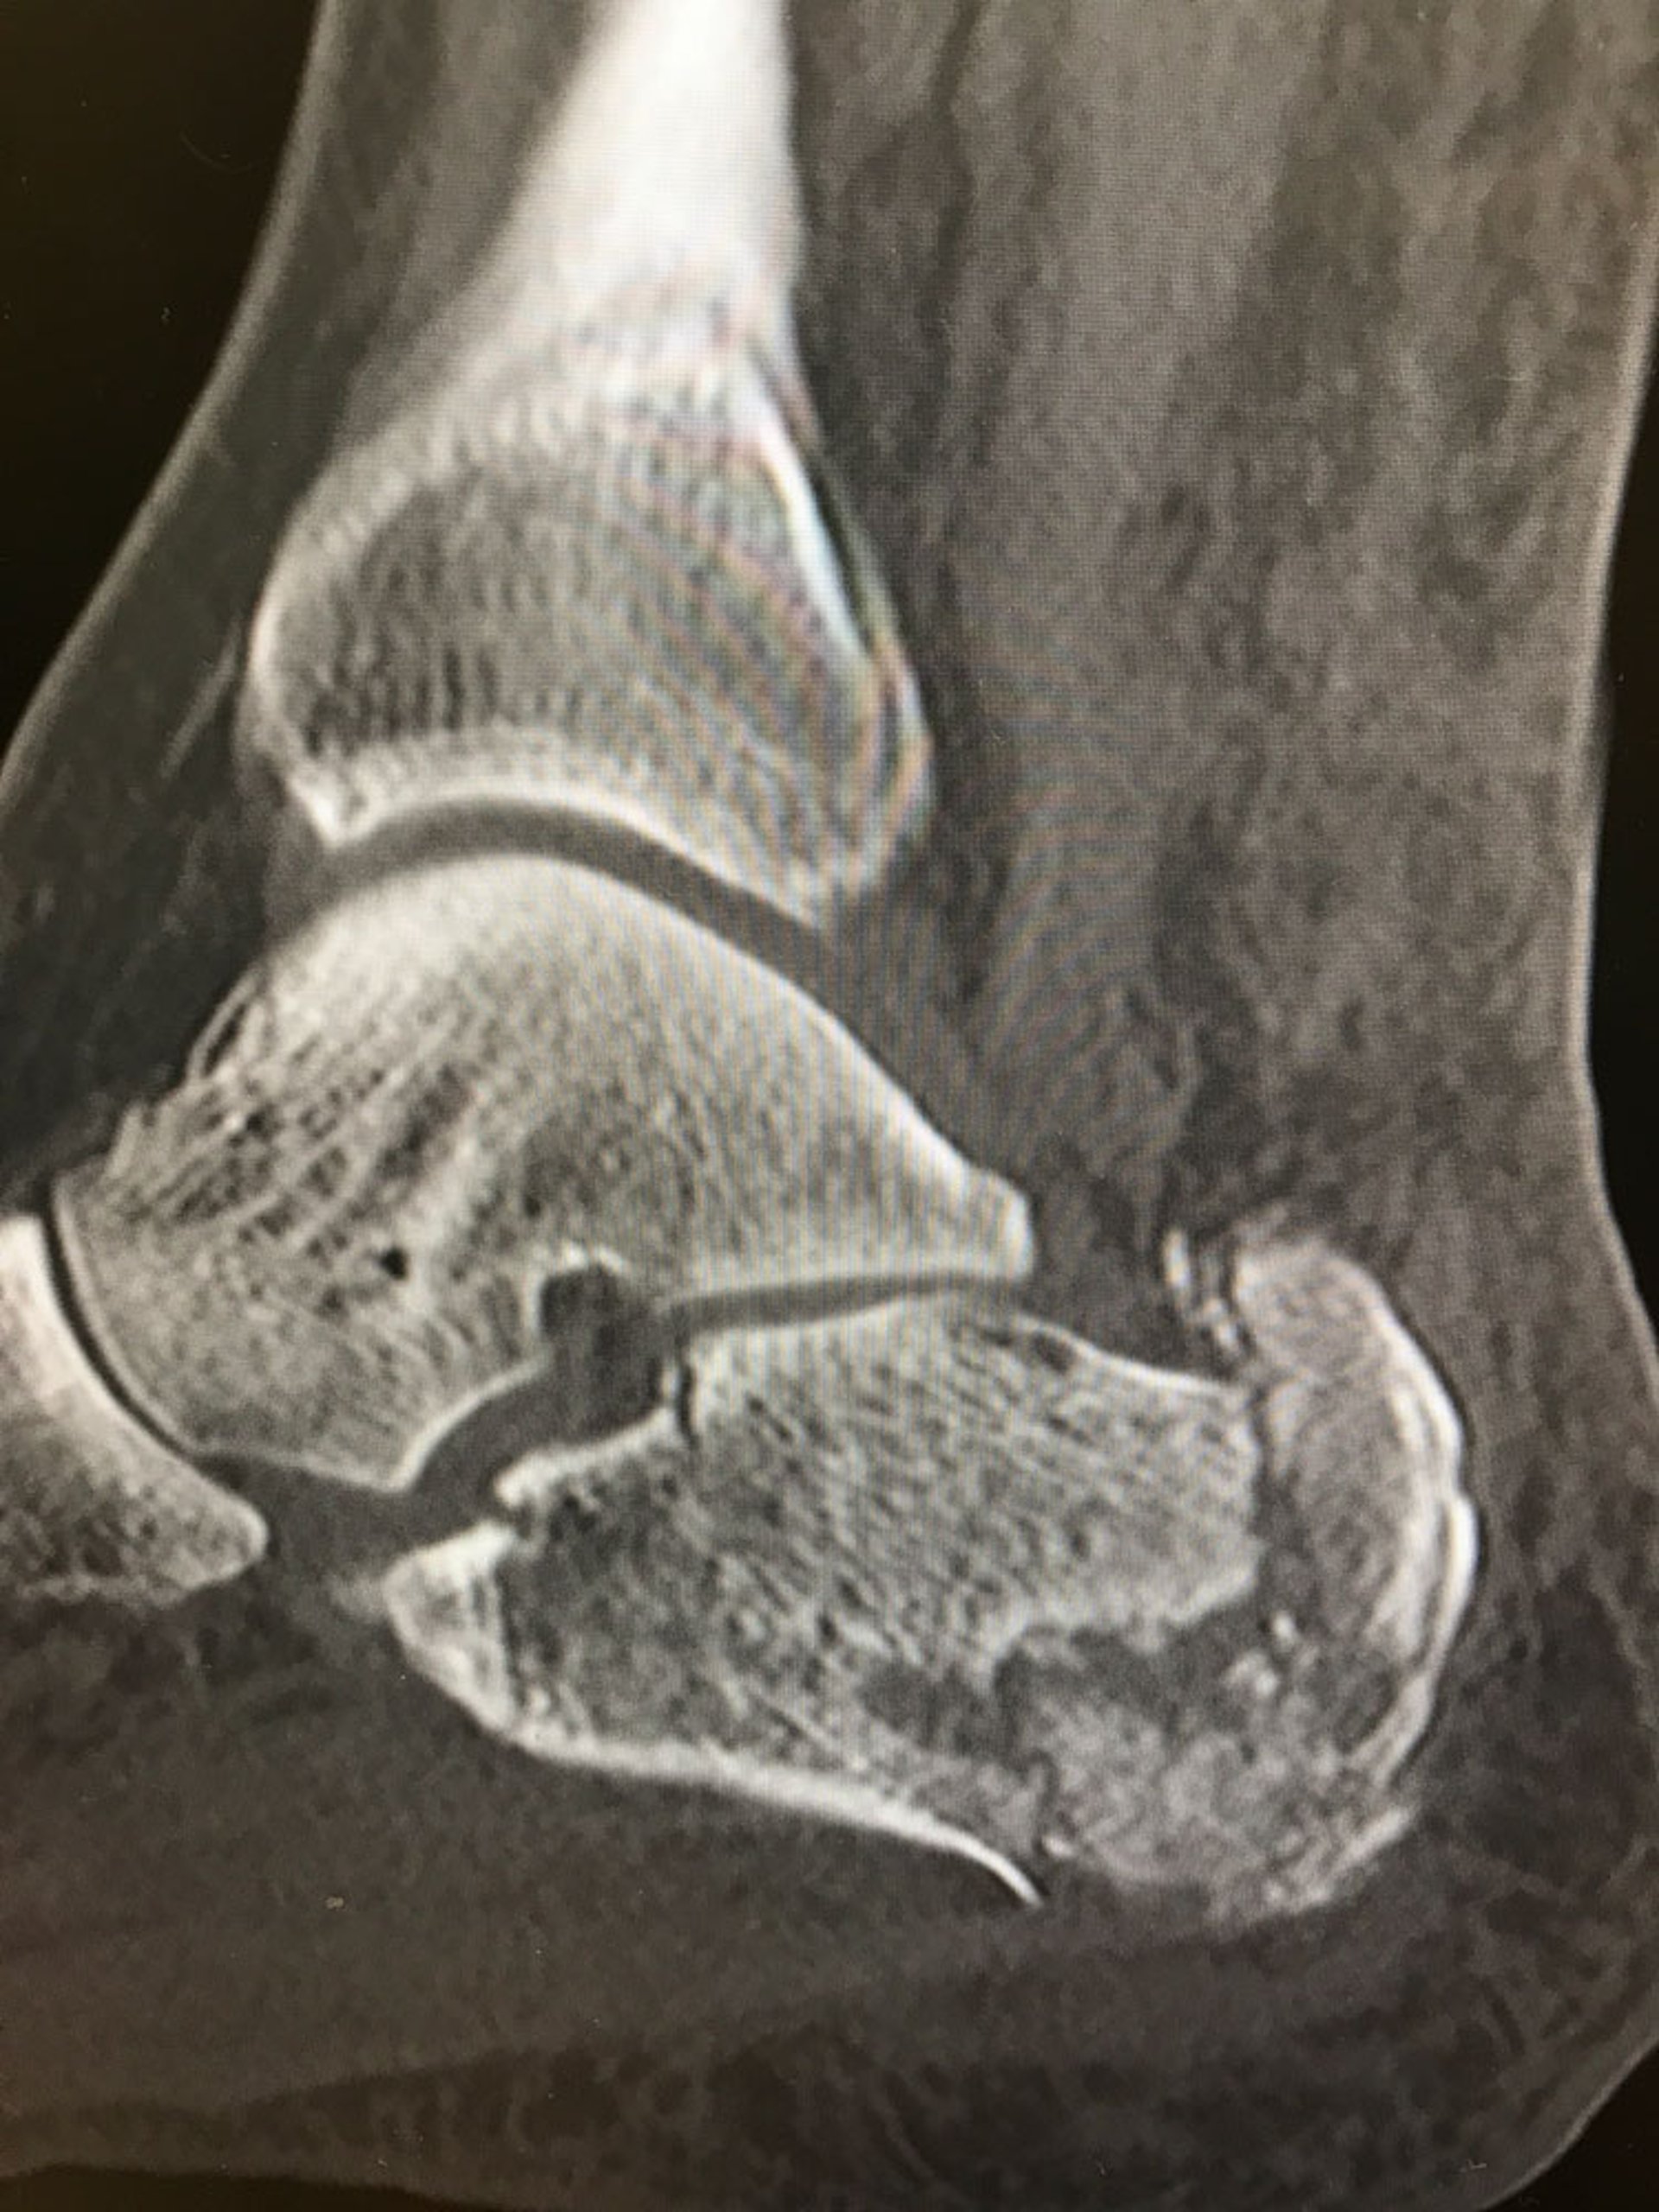

This radiograph shows a comminuted fracture of the calcaneus.

Image courtesy of Danielle Campagne, MD.